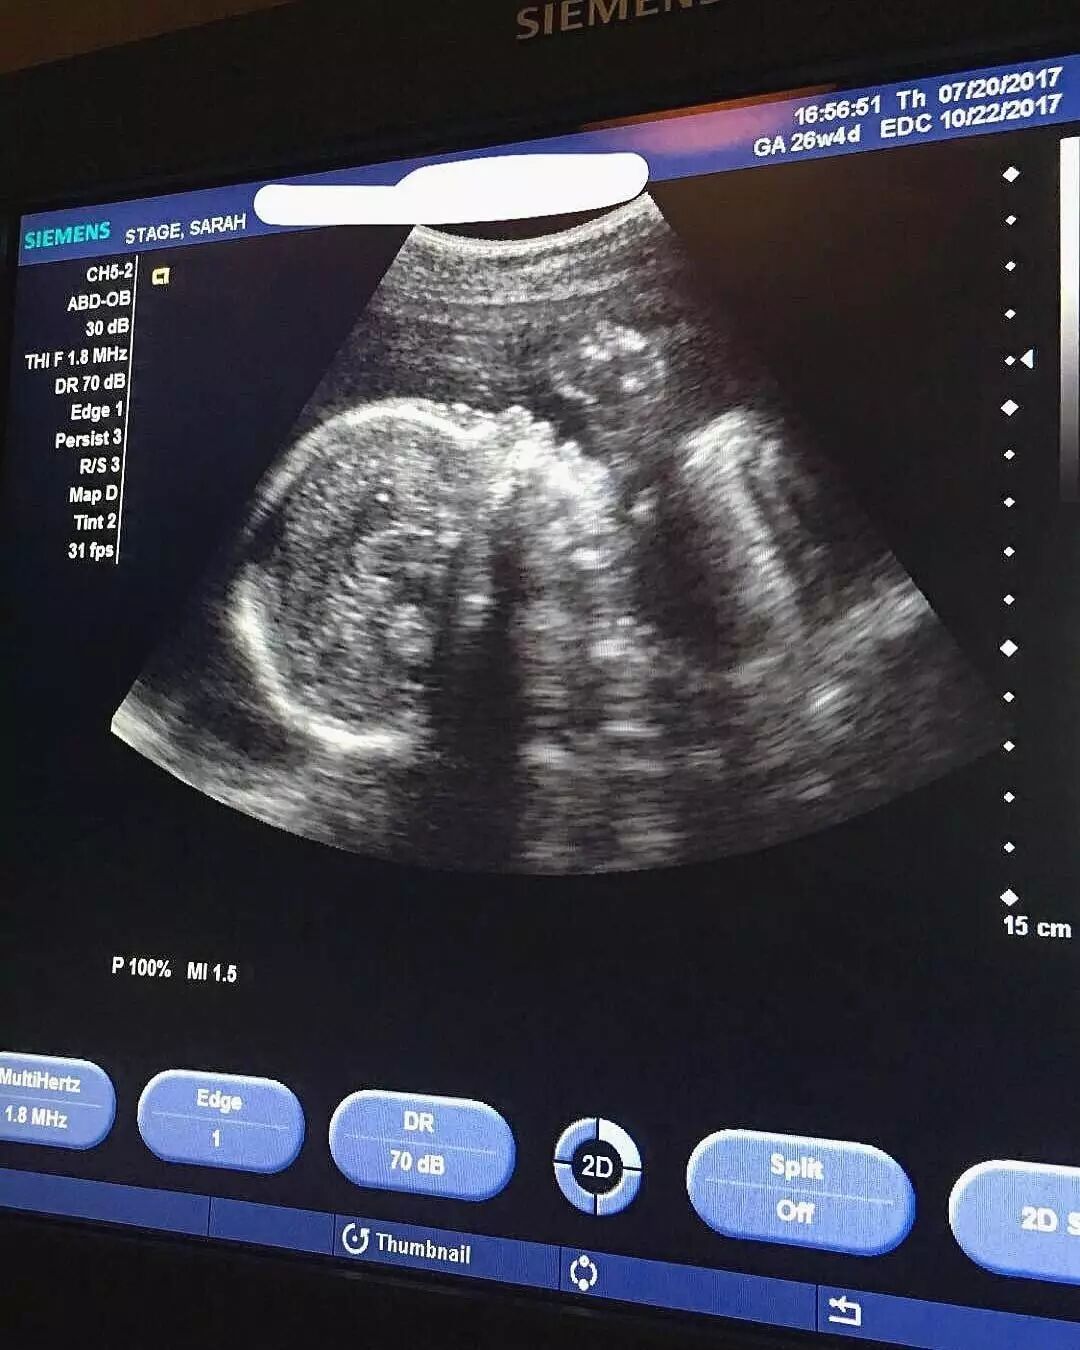

无奈Sarah只能PO出了孕检照片,

宝宝一切正常,

而且心跳强劲有力,

目前很健康。

并霸气配文,

“怀自己的孕,让别人说去吧。”